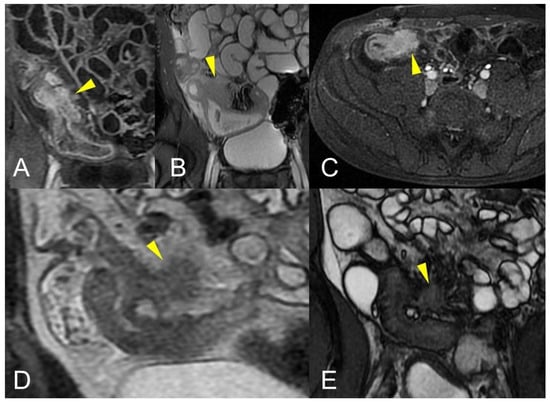

Figure 9.

Pathological junctions of intestinal segments through enteroenteric fistulas, which represents internal fistulas that connect intestinal segments such as ileo-sigmoidal (A) and ileo-colic (B).

Unlike the sinus tracts, a fistula is defined as a pathologic channel connecting two or more epithelialized surfaces [11]. Fistulae can be simple (single extra enteric tract: enter enteric, enter colic, enter vesical, enterocutaneous, or rectovaginal) or complex (branching and intersecting fistulas, sometimes with a star-like appearance [5]). They represent a complication in approximately 14–50% of the patients with Crohn’s disease (Figure 9, Figure 10 and Figure 11).